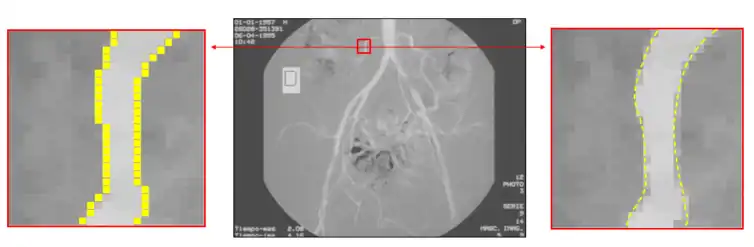

Отже, чітко вказати певний поріг того, наскільки великою має бути зміна яскравості між двома сусідніми пікселями, щоби ми могли сказати, що між цими пікселями має бути контур, не завжди просто.[4] Справді, це одна з причин, чому виявляння контурів може бути нетривіальною задачею, якщо тільки об'єкти в сцені не дуже прості, а умови освітлення можливо добре контролювати (див., наприклад, контури, виділені в зображенні з дівчинкою вище).